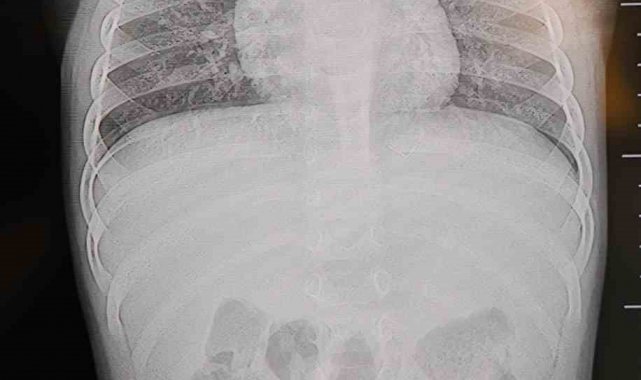

Baba Poyraz, bir gün acil serviste yapılan kontrollerde bebeğin belinde yabancı cisim olduğunu, çekilen filmlerde ise "L" şeklinde zımba teli tespit edildiğini söyledi. Çeşitli hastanelere yönlendirildiklerini anlatan baba, uzun süre müdahale edilmediğini, daha sonra özel bir hastanede yapılan operasyonla zımba telinin çıkarıldığını kaydetti.

Poyraz, bebeğin doğduktan sonra sarılık diyerek kuvöze alındığını belirterek, "Bir hafta orada yattı. Sonra çıkardılar, eve getirdik. Eve geldikten sonra gece gündüz ağlaması hiç durmadı. Tekrar hastaneye götürdüm. Kaşınıyordu, bir hafta banyo yaptıramadık. Sonra duş aldırdım, bağırması daha da arttı. Belini açtık, sırtına baktık, bir şey var mı diye kontrol ettik, görünürde yoktu. Hastaneye götürdük, şurup verdiler. Aylar geçti. Daha sonra acilde bir doktor çocuğumun belinde yabancı cisim olduğunu söyledi. 184'ü aradım, şikayette bulundum. Başhekim yardımcısının yönlendirmesiyle tomografi çekildi. O zaman belinde zımba teli olduğu netleşti. Başka bir hastaneye götürdük, 'riskli, 8 yaşına kadar alınamaz' dediler, geri gönderdiler. Eve geldikten üç gün sonra oğlum bayıldı. Kardeşimle özel hastaneye götürdük. Orada filmlere baktılar, 'akciğere doğru gidiyor, L şeklinde zımba teli var, alınması lazım' dediler" dedi.